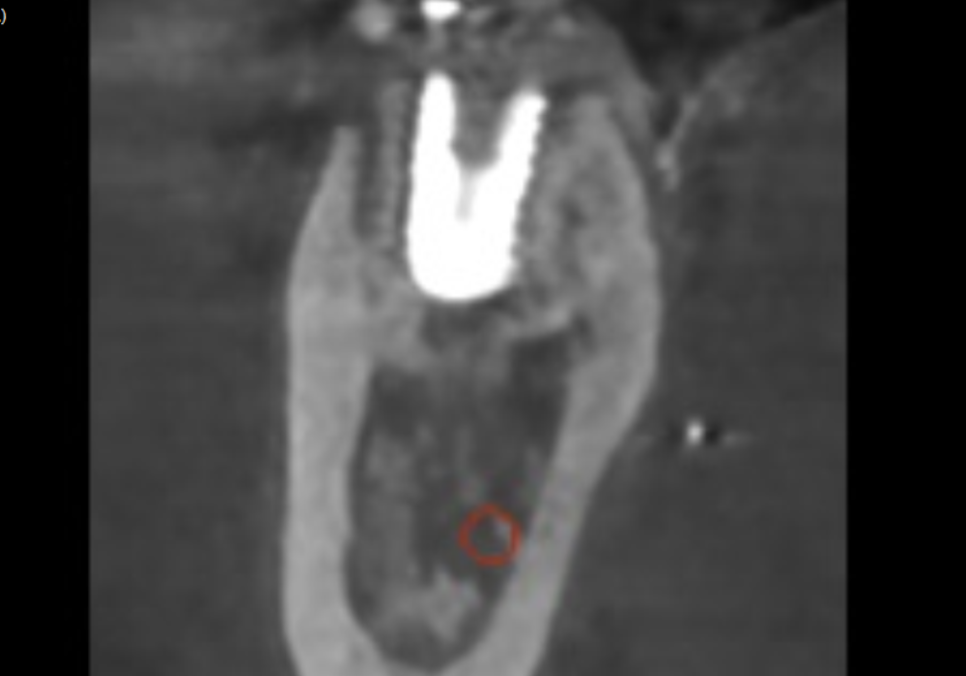

CT를 살펴볼게요~

241015

혹시 앞서 보여드렸던 환자와의

차이점을 눈치채셨나요?

빨간 동그라미로 표시한 하치조 신경인데요.

이 신경과 뿌리 끝 사이의 뼈가

확실히 뼈가 꽉 차 있고

하얗게 밀도가 높은 느낌이 들죠~?

이 환자분은 뿌리 끝에 염증이

있었던 게 아니라,

치아 자체가 약해 뿌리만 부러진 상태였기에

주변 뼈는 아주 건강하게 남아 있었습니다.

이렇게 토대가 튼튼하다면

치아를 뽑는 당일 임플란트를 바로 심을 수 있어요.